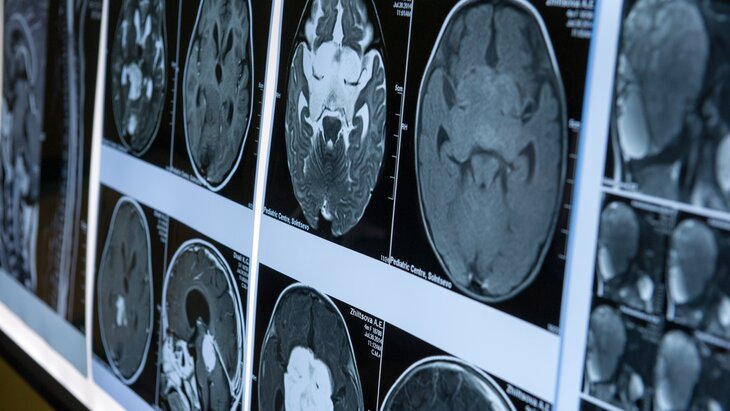

Ученые из Москвы и Санкт-Петербурга разработали уникальный сенсор для магнитоэнцефалографии – измерения магнитной активности головного мозга. Новый прибор, который создадут на его основе, увеличит точность исследований в несколько раз, снизив стоимость производства.

Магнитоэнцефалография позволяет на самой ранней стадии диагностировать такие заболевания как эпилепсия, болезни Паркинсона и Альцгеймера. Кроме того, у прибора есть исследовательский потенциал. Он позволит получить новые данные об устройстве мозга и процессах, протекающих в нем при мыслительной деятельности.

Основа современных магнитоэнцефалографов – сверхчувствительные сенсоры, для работы которых нужны сверхнизкие температуры. Их помещают в своеобразный термос с гелием, что делает оборудование получается очень громоздким и дорогим в эксплуатации. К тому же сенсоры невозможно поднести к голове человека ближе чем на три-четыре сантиметра. При этом в исследования вмешивается магнитное поле Земли, поэтому измерения приходится проводить в специальной магнитоизолирующей комнате. Лучшего способа у человечества нет, метод позволяет зарегистрировать всплески активности нейронных групп длительностью менее 10 миллисекунд с пространственным разрешением в несколько миллиметров.